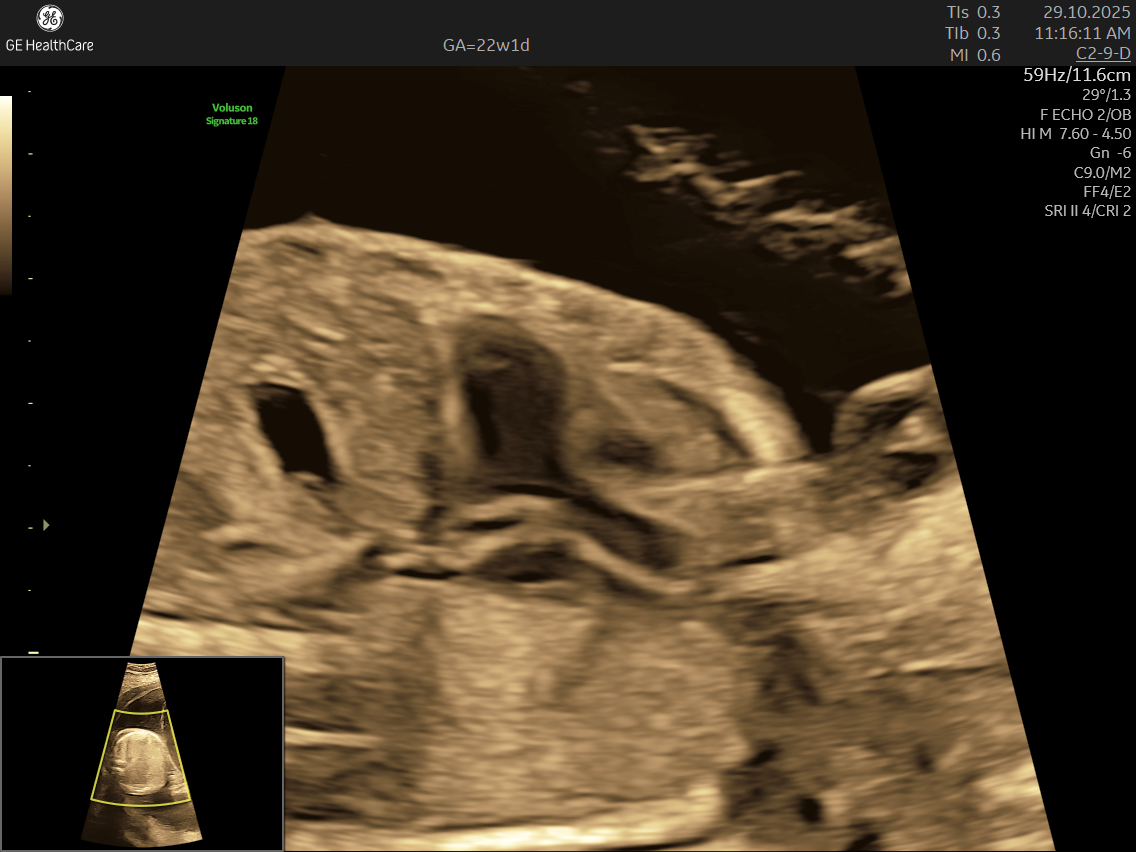

- High Detail: Utilizing advanced Doppler ultrasound technology, it tracks blood movement through the heart and valves, highlighting issues that general scans often cannot detect.

- Specialized Equipment and Expertise: Performed with high-resolution machines and by specialist doctors, fetal echocardiography pinpoints tiny structural or functional abnormalities that conventional scans may miss—helping ensure early, accurate diagnosis and informed planning.

- Using the advanced GE Voluson S10 ultrasound machine—renowned for its superior imaging clarity, 4D real-time visualization, and automated analysis tools that significantly increase diagnostic accuracy and reduce the chances of missing subtle heart defects.

- Its a specialized ultrasound done between 18–24 weeks of Gestational Age that evaluates the structure, function, and rhythm of a baby’s heart while still in the womb. This scan uses high-frequency sound waves to create detailed images of the fetal heart, aiding in the detection of congenital heart defects (CHDs) and other abnormalities.